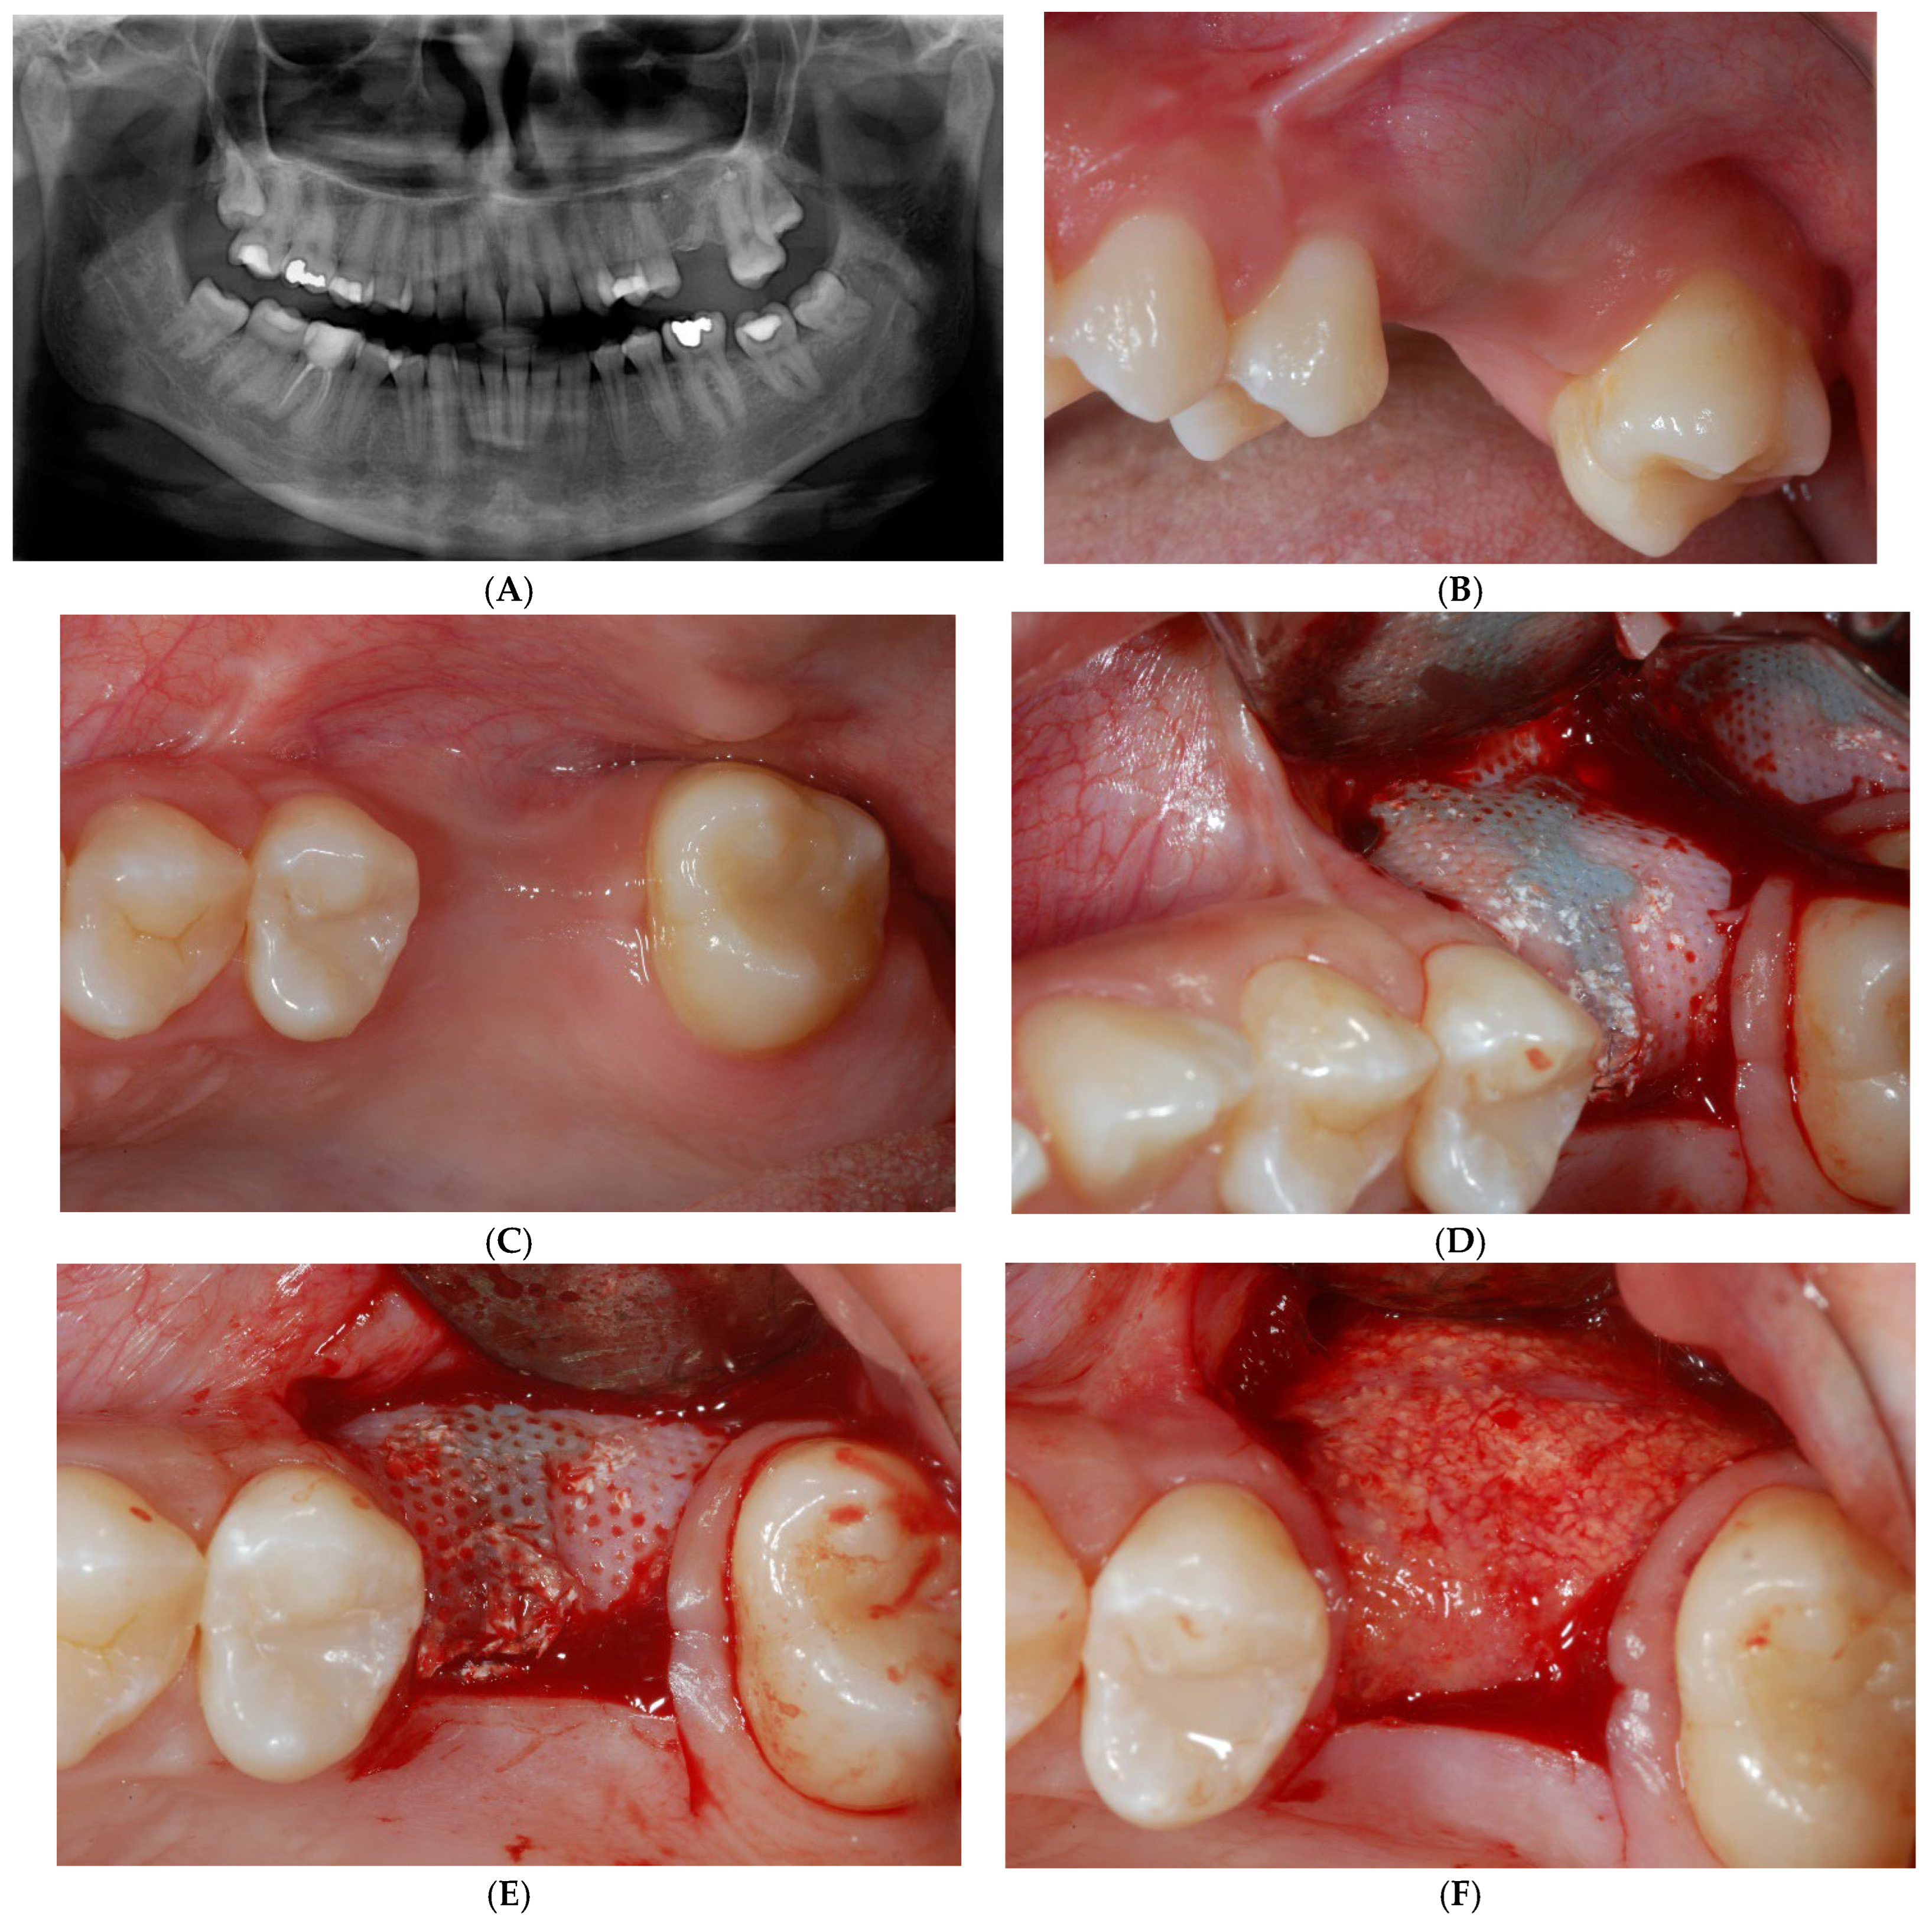

Treatment options were discussed, and the patient signed a consent form for the tooth extraction and the subsequent augmentation procedure, to be scheduled as a staged approach for implant site development. Four months after the tooth extraction, soft tissue healing reached a proper maturation (Figure 2A,B), and a new CT was requested to evaluate the wound healing and bone availability for implant therapy. The CT scans revealed a horizontal ridge defect (Figure 2C,D–F) that required correction with a staged GBR procedure.

Figure 2.

Soft tissue healing four months after tooth extraction (A,B). New CT was requested to evaluate wound healing and current bone availability for implant therapy. CT scans revealed horizontal ridge defect (C–F) that had to be corrected with a regenerative procedure.

After making the crestal incision, two vertical buccal releasing incisions—mesial to the second premolar and distal to the second molar—were performed. Then, a mucoperiosteal flap was raised, revealing the wide ridge deficiency (approximately 5, 7, and 9 mm in the mesio-distal, bucco-palatal, and corono-apical directions, respectively), highlighting the impossibility of achieving proper implant stability (Figure 3A,B). Then, a copious bleeding recipient site was created by bur perforations through the medullary spaces. A TR-dPTFE membrane (Cytoplast® Ti 250 Buccal, Osteogenics Biomedical, Lubbock, TX, USA) was shaped and trimmed with scissors to fit the ridge defect (Figure 4A), taking care to position the membrane edges 1.5 mm away from the adjacent roots, and stabilized with two pins on the buccal side. A graft of 100% NH embedded in a silica gel matrix (NanoBone® Artoss, Rostock, Germany), in the form of 0.6 × 2 mm granules, wetted with sterile saline (Figure 4B), was applied and compacted with a spoon/plugger tool to avoid leaving voids, but without over-compacting the material (Figure 4C). The membrane was moved to the palatal side and stabilized with an additional pin to the palatal bone wall (Figure 4D,E). A continuous periosteal incision along the entire length allowed the buccal flap to move coronally, followed by tension-free suturing using horizontal mattress and single stitches (Figure 5A) with PTFE material (Cytoplast® suture, Osteogenics Biomedical, Lubbock, TX, USA), which were removed 14 days later (Figure 5B). Healing was uneventful, and after a period of 10 months (Figure 6A–C), the site was re-opened for membrane removal and implant insertion. A smaller paramarginal trapezoidal mucoperiosteal flap, sparing the periodontum of the adjacent teeth, was raised (Figure 6D,E). The membrane was easily removed, and the defect appeared to be completely regenerated (Figure 6F). A 4 mm wide trephine bur (Stoma®, Emmingen-Liptingen, Germany) was used to harvest a bone biopsy (Figure 7A), measuring 3 mm in diameter and about 6 mm in length (Figure 7B), so as not to extend the future implant bed preparation. The implant bed was then definitively prepared with the drill dedicated to the chosen implant (Figure 7C), a 5.0 × 9 mm implant (Camlog® Screw Line Promote Plus Biotechnologies, Basel, Suisse). The bone biopsy was immediately fixed in 10% neutral buffered formalin and stored at room temperature. The specimen was then decalcified in formic acid, dehydrated in progressively more concentrated ethanol, and finally embedded in paraffin. Sections of 5–6 µm thickness were cut with a microtome (Leica SM 2.400, Solms, Germany) and stained with hematoxylin and eosin and the Azan–Mallory staining technique for light microscopy. Histological evaluation and photo documentation were performed using the Axiophot microscope (Zeiss, Göttingen, Germany) at 12.5×, 25×, 100×, 200×, 400× magnifications.

Figure 3.

After buccal flap reflection with two vertical releasing incisions, wide horizontal bone defect was evident (A,B).

Figure 4.

Titanium-reinforced dense polytetrafluoroethylene (TR-dPTFE) membrane was shaped and trimmed with scissors to fit ridge defect (A) and stabilized with 2 pins on buccal side. Particulate graft of 100% nanocrystalline hydroxyapatite (NH) embedded in a silica gel matrix, wetted with sterile saline (B), was packed to fill defect (C). Membrane was moved to the palatal side and stabilized with additional pin to palatal bone wall (D,E).

Figure 5.

Tension-free suture with horizontal mattress and single PTFE stitches was obtained (A). Sutures were removed 14 days later (B).